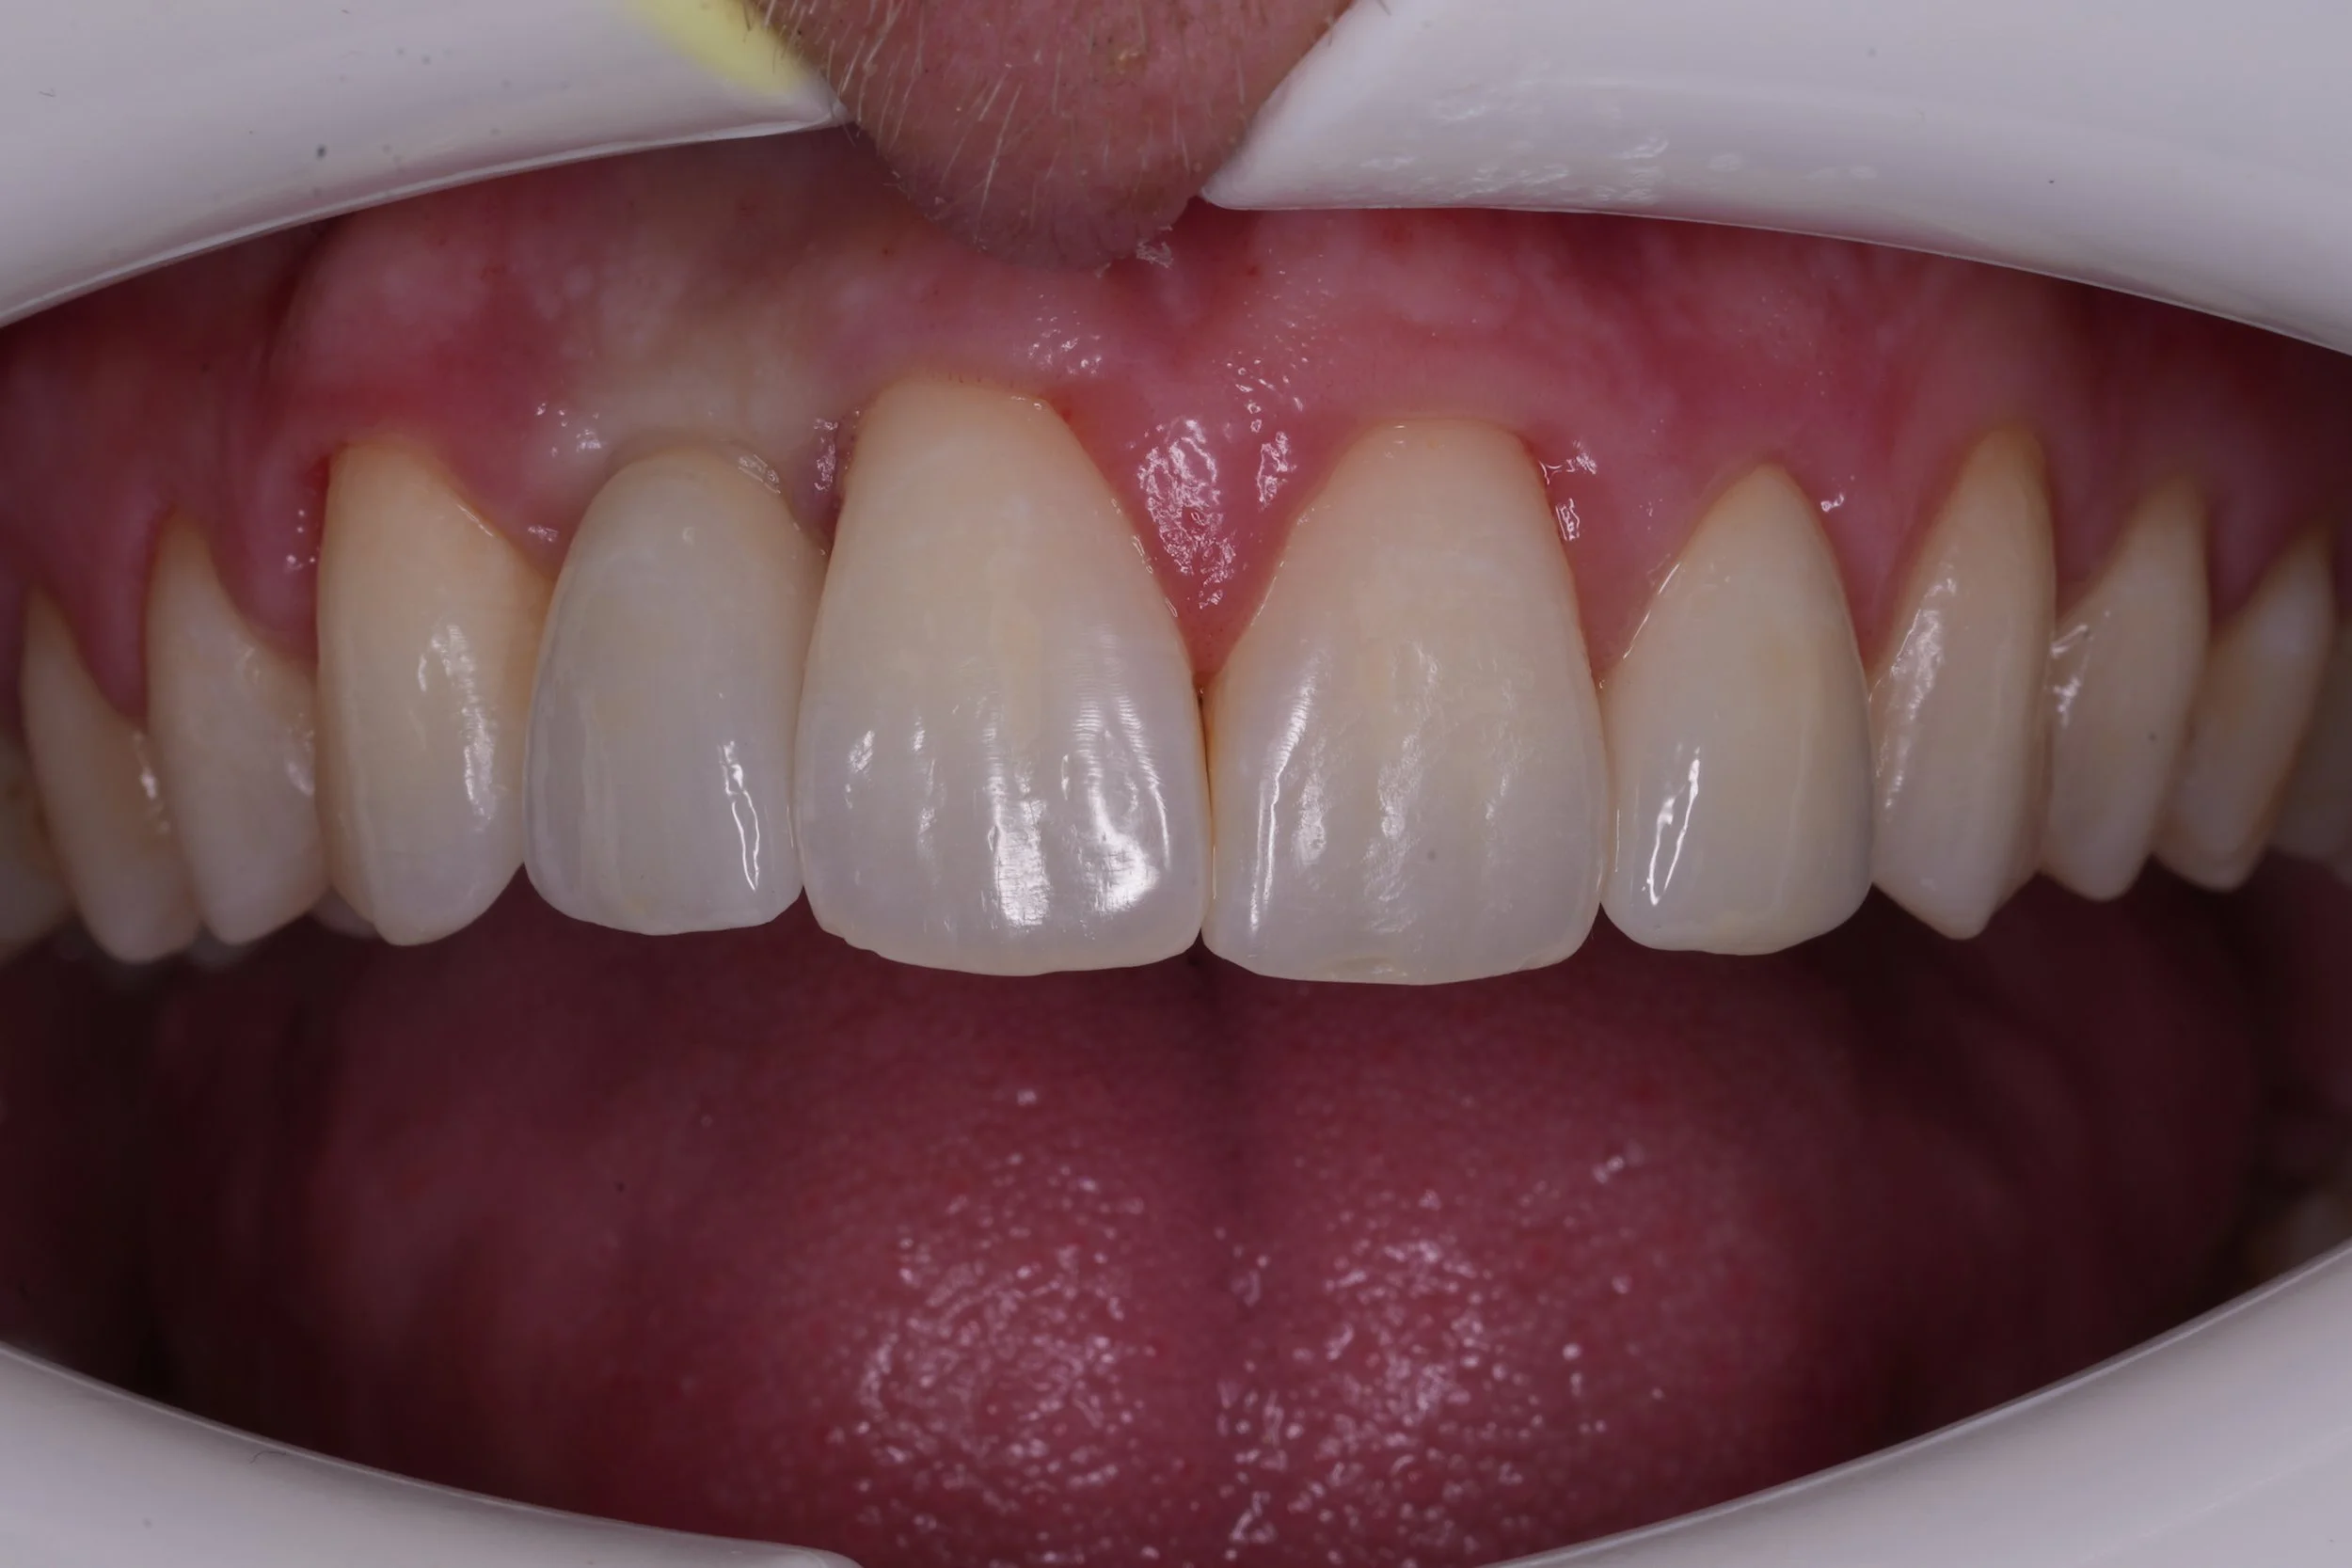

Fixed pros

Dental Implants